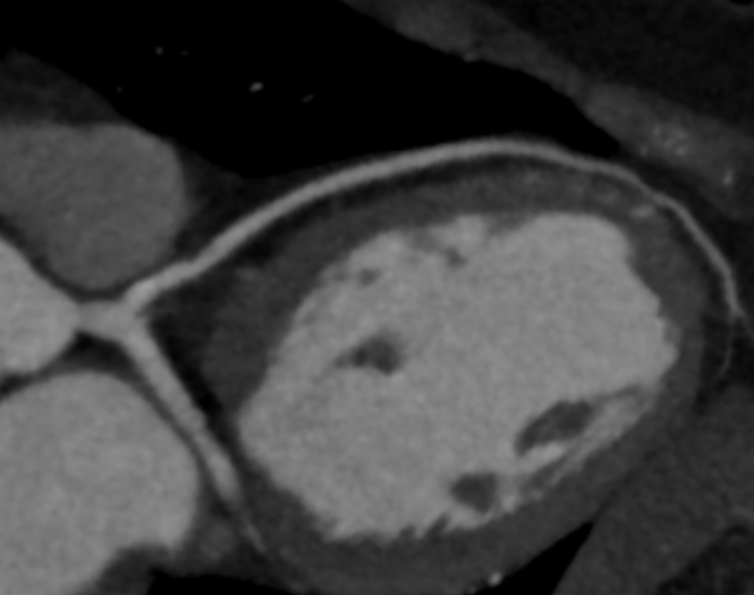

Διεξάγεται σε αξονικό τομογράφο πολλαπλών τομών (>128 detectors) με εξειδικευμένο λογισμικό απεικόνισης και επεξεργασίας των δεδομένων της παλλόμενης καρδιάς. Με την χρήση ακτίνων Χ, υπό ηλεκτροκαρδιογραφικό συντονισμό, διεξάγεται λήψη εγκάρσιων τομών της καρδιάς και με ειδική επεξεργασία δημιουργείται τρισδιάστατη εικόνα του καρδιακού μυ, των καρδιακών βαλβίδων και των στεφανιαίων αγγείων. Στον εξεταζόμενο χορηγείται σκιαγραφική ουσία που δίνει την δυνατότητα ανάδειξης στένωσης ή άλλων ανωμαλιών στις αρτηρίες.

Ακρογωνιαίος λίθος της διαγνωστικής αξίας της αξονικής στεφανιογραφίας είναι η δυνατότητα χαρακτηρισμού των αθηρωματικών πλακών (επασβεστωμένες, μικτής σύστασης, μη-επασβεστωμένες) ανάλογα με το ποσοστό εναπόθεσης ασβεστίου σε αυτές που καθοδηγεί την μετέπειτα κλινική απόφαση και θεραπεία.